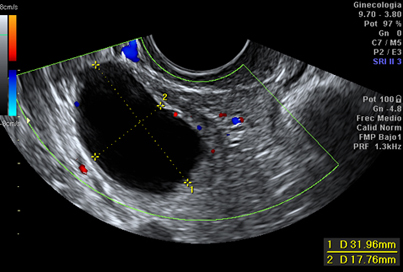

Hospital Universitario Quirónsalud Madrid ofrece la posibilidad de realizar ecografía ginecológica de alta resolución para la caracterización y estudio de patología encontrada durante exploraciones ginecológicas rutinarias, como quistes ováricos, pólipos endometriales, miomas, etc.

El estudio mediante tecnología doppler (que permite el estudio de los vasos sanguíneos y las características de la circulación de la sangre) y tridimensional complementa el estudio con la ecografía de alta resolución, y ofrece la posibilidad de realizar un diagnóstico más exacto de los hallazgos durante la exploración ecográfica.

Ecografía ginecológica que muestra un quiste ovárico.